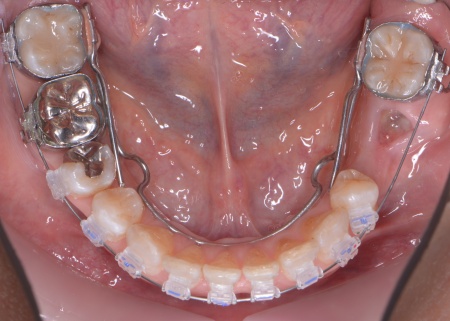

①上あごの骨が狭く歯が並ぶスペースが不足しているため、まず上あごの骨の幅を広げる急速拡大装置を装着する。

成人になってからの骨の拡大は難しいものの、あごの骨に矯正用の小さなネジを埋め、そこを固定源として効率的に歯を動かす治療を併用することでスムーズに拡大を進める。

②①と並行して上下歯列にワイヤー矯正のマルチブラケット装置を装着し、歯並びと噛み合わせを整える。